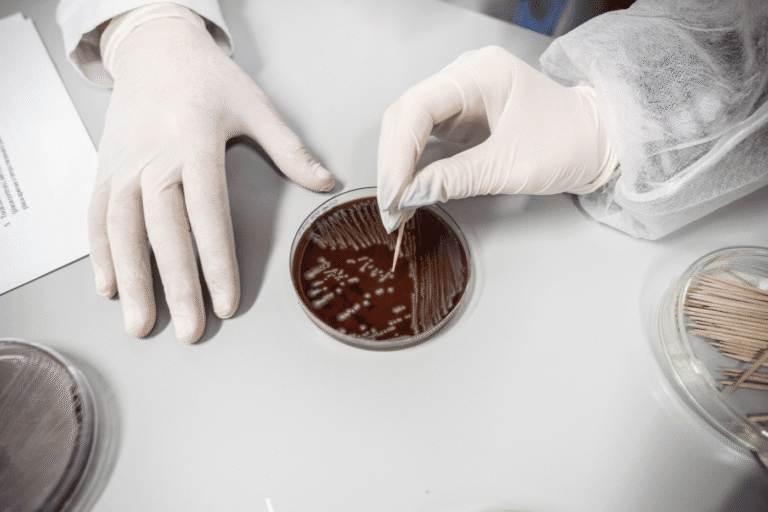

Como uma equipa da UMinho está a criar o antidepressivo do futuro com ‘cogumelos mágicos’

Luísa Pinto e a sua equipa no ICVS garantem um financiamento de prestígio para desenvolver tratamentos rápidos e duradouros, com potencial para reverter a lentidão dos atuais fármacos psiquiátricos.